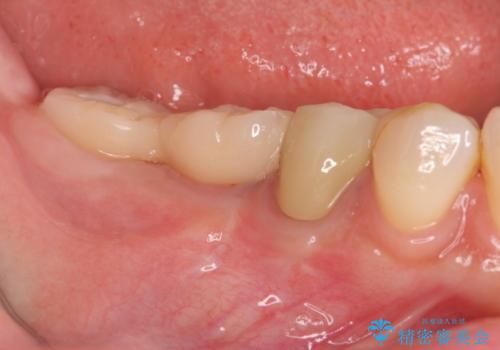

- 「数年前に入れたブリッジがぐらぐらする、診て欲しい。」と来院されました。

ブリッジを支える歯が割れてしまい、抜歯が必要であることと、骨の大きな吸収が見られました。

インプラント治療を行うにあたり周囲に骨を造成することで安定して噛める環境の整備を計画します。